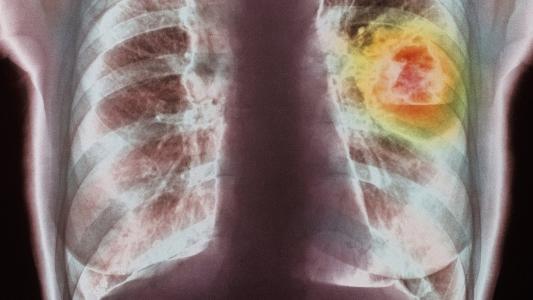

基因靶向药物与晚期肺癌之间的战争

新的临床试验发现,两种靶向遗传缺陷的药物,正在给予具有特定类型晚期肺癌患者生存期更长,提高生活质量的新希望!